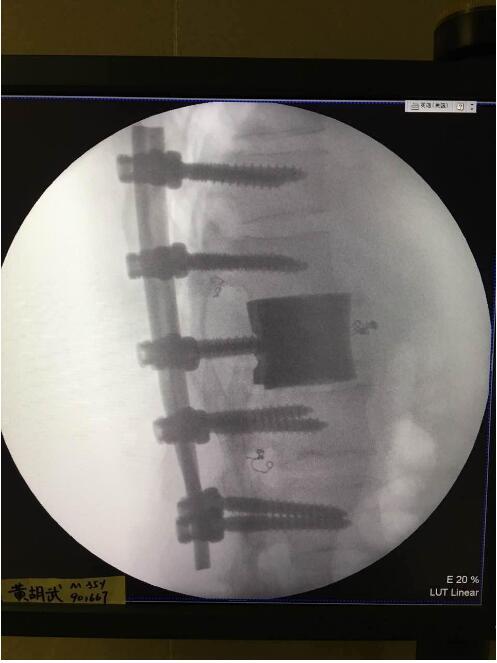

这次手术是广州华钛三维骨科研究中心(华钛三维骨科研究院)与南方医院联合澳大利亚技术科学与工程院吴鑫华院士领导的莫纳什大学增材制造研究中心合作的世界第一例3D打印个性化"人工椎体/腰间盘一体化"植入手术。南方医院脊椎及骨病外科郑明辉副主任医师在岭南名医陈建庭主任和朱青安教授指导下,与华钛三维工程师陆国赞合作构思设计,澳大利亚莫纳什大学增材制造研究中心主任吴鑫华院士团队进行了一个多月的个性化钛合金3D打印工艺研究,成功打印出符合病人要求的人工椎体/腰间盘一体化"植入物。这次手术的成功,标志着中国的3D打印植入物技术在骨科医疗领域达到世界先进水平。

为了更好的完成手术,陈建庭主任、郑明辉副主任医师等骨科专家与华钛三维的3D打印专家从2017年10月份开始筹备该手术。考虑到每一个病人的脊椎形状都存在差异,骨科专家认为用一个现成的标准植入物不大可能匹配病人的生理参数。医学专家和3D打印专家根据病人脊柱的CT扫描数据,为病人的脊柱建立了精准的3D图像。根据这个图像,治疗团队就能够设计并定制出属于病人的个性化植入物。为了使个性化定制的人工椎体与病人椎体之间更好的融合,手术实施前治疗团队先后设计了100多个方案,制作了数十个植入物的术前模型进行研讨。事实证明,手术最终使用的植入物是最适合手术和病人身体情况的。

郑明辉医生表示,因外伤、肿瘤等因素导致的骨、关节损害,为治疗所建立骨支架必须借助弧型板、螺丝钉、人造骨及关节等,而这些植入物要长期留置于人体内,会受到人体的弯曲、扭转、挤压、肌肉收缩力等作用,所以要求植入物具有高的强度和韧性,研究与临床实例证明,在人体受力小的部位可以用纯钛,在人体受力大的部位可以用Ti-6Al-4V合金,完全可以满足人体植入物的要求。该3D打印人工椎体特殊之处在于其海绵状的微孔结构结合拓扑框架结构。有了这种内嵌拓扑框架金属“骨小梁”,既使相邻正常脊椎的骨细胞可以长入其中,最终实现骨融合,又保证了椎体的整体力学性能。

利用3D打印技术生产出来的人工椎体是完全按照患者的解剖结构完成脊椎结构重建及固定的, 装上一枚精准的、个性化的人工脊椎,患者康复后完全可以正常地生活和工作。过去这种手术常常是使用钛网内填入自体或异体碎骨作为椎体间支撑材料,但钛网一旦移位压迫脊髓,患者就会有瘫痪的风险。这次手术中的脊椎植入物内部具有经过力学优化设计的晶格结构,比传统钛网具有更强的承重力,金属3D打印可以直接制造出这样的复杂结构。

最终在经历近八个小时后,病人的家属终于等到了好消息:人工椎体/椎间盘一体化金属植入物成功植入,手术顺利。由于病人术中出血量小,生命体征平稳,他不用进入ICU观察,直接回到了普通病房。“现在我们都很高兴,成功做出了世界首例人工椎体/椎间盘一体化金属植入物,病人今后可以与常人一样工作和生活。”郑明辉医生说。